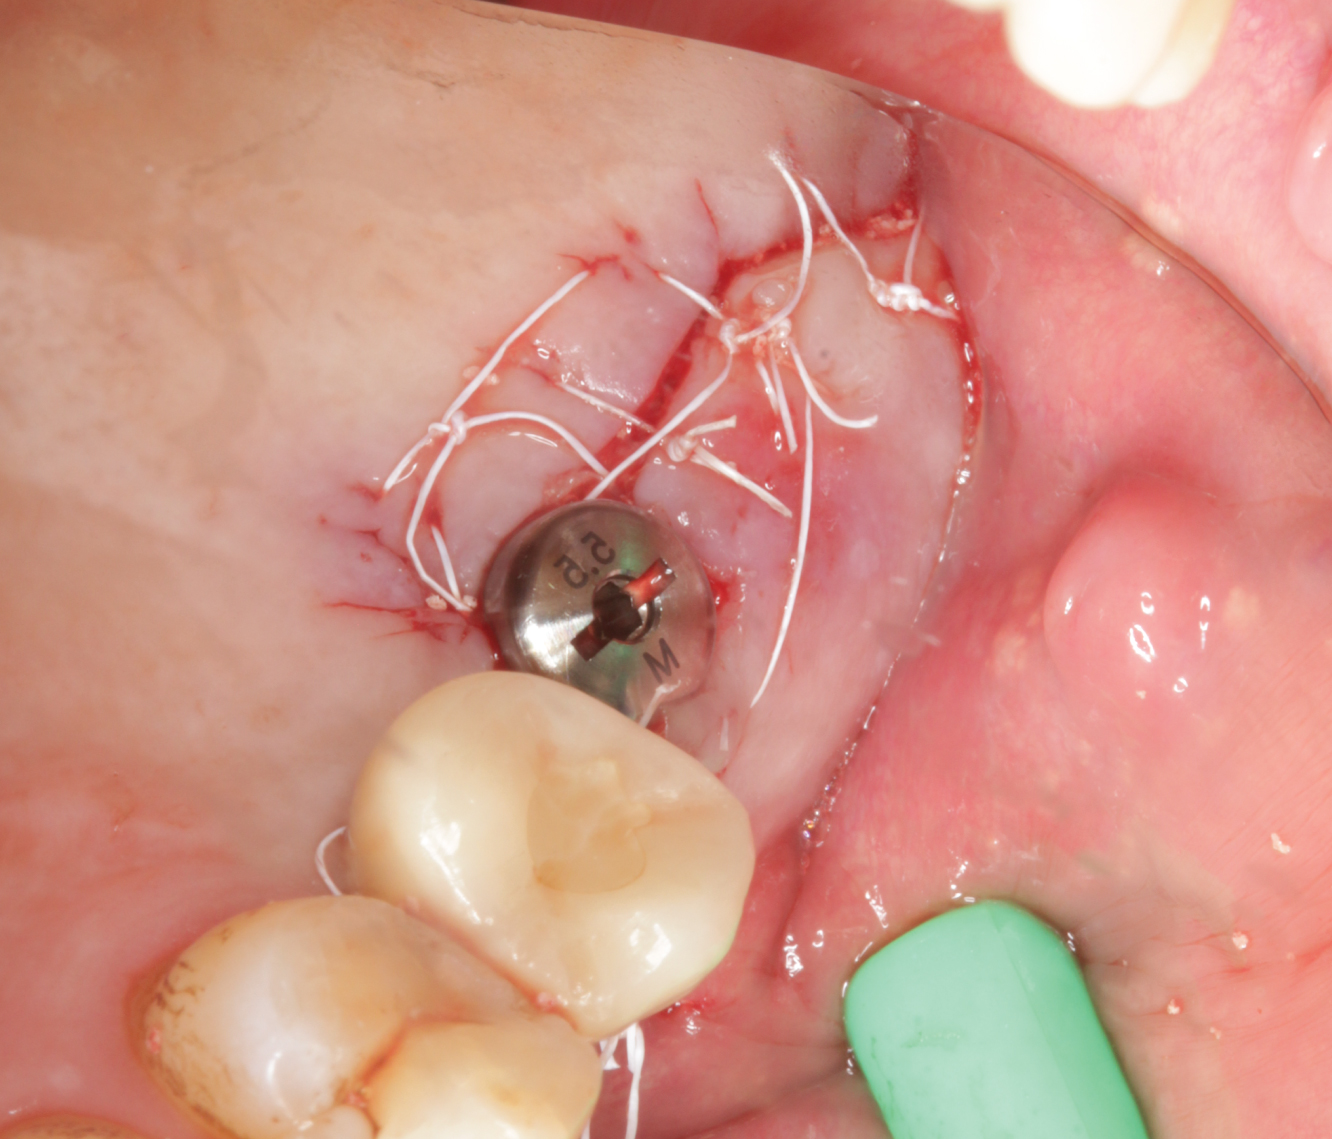

Director’s Clinical Cases

Director’s Clinical Cases